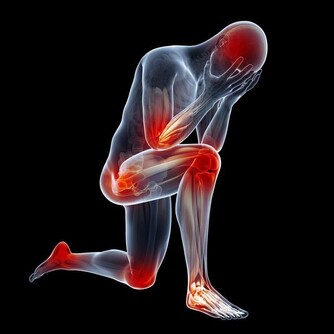

為了時尚、個性,有的女人一年四季都穿裙裝,膝蓋和關節暴露在外,難免遭受風、寒、濕等外邪的侵擾,引起關節疼痛。

很多這樣的女性,她們歲數都不大,但早早就有了腿痛的毛病。

關節部位受寒疼痛,可不是一天兩天形成的,正所謂,冰凍三尺非一日之寒。

本來膝關節受寒是老年人的「專利」,所以有「老寒腿」之說,但現在「老寒腿」也開始瞄上了中青年男女,希望大家在天氣比較寒冷的時候,一定要注意呵護自己的雙腿,在讓別人欣賞美麗的同時,也讓自己擁有一份健康和活力。